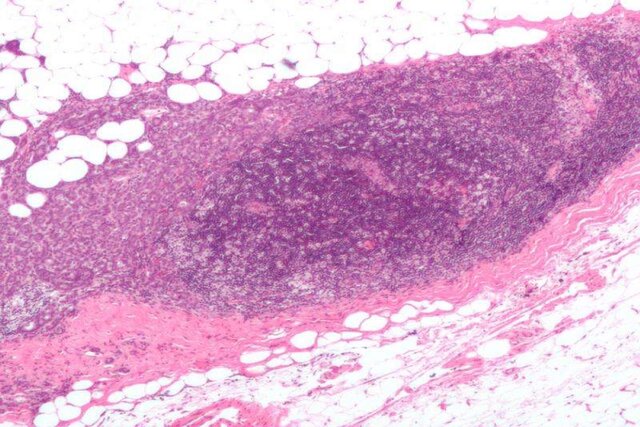

سرطان پستان شایعترین سرطان در جهان است. سازمان بهداشت جهانی تخمین زده که در سال 2020 نزدیک به هشت میلیون زن در سراسر جهان مبتلا به سرطان پستان بودهاند که طی پنج سال اخیر از ابتلای خود به این بیماری آگاه شده بودند. کشف روشهای تشخیصی جدید اهمیت زیادی در تلاش برای به حداقل رساندن آثار مخرب این بیماری دارد. محققان دانشگاه لاهور پاکستان به بررسی نقش نشانگرهای التهاب و استرس در ایجاد و پیشرفت سرطان سینه پرداختند.